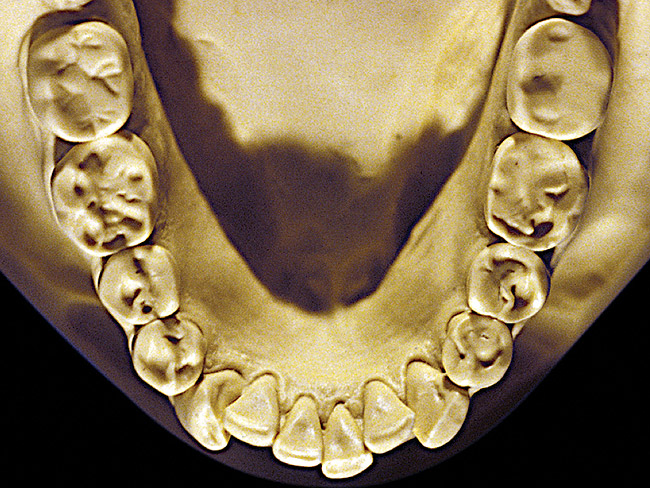

Figure 12  Advanced NCLTS from toothpaste, mandibular arch.

Figure 12

Figure 7 and Figure 8 are examples of NCLTS resulting from toothpaste. Upon examination, one could see that the overall anatomical detail of the teeth was faded with a sandblasted appearance. A closer view of the facial surfaces (Figure 9 and Figure 10) illustrates this to a greater degree and one can observe that the normal intricate facial anatomy was completely missing. It is interesting to note there was no cervical recession of the gingiva, even though every surface of every tooth had been abraded. This is due to the fact that this patient had always used a soft, round-ended filament toothbrush.21-22 This patient's sole desire regarding her oral hygiene was to get her teeth whiter.

So that the previous example is not misleading, the behavioral profile of the toothpaste abuser is not necessarily the "caries-free immaculate oral hygiene patient," but can be virtually anyone who brushes their teeth with toothpaste. Figure 11 and Figure 12 illustrate a more advanced example of toothpaste abuse showing a patient with multiple restorations and some unkempt teeth. The anatomical details were faded with a sandblasted appearance and the silver alloy restorations were highly polished. The facial surfaces of the mandibular canines and premolars were affected the most, creating the pathognomonic pattern. Figure 13 and Figure 14 are a close-up view of this area, illustrating a cupping or cratering effect, but of the asymmetrical variety. This patient did not like the color of his teeth and spent an inordinate amount of time brushing his teeth. Again, likewise due to the exclusive use of a round-ended, soft-bristle toothbrush, note there was no cervical gingival recession in this case either. When the featured casts illustrating toothpaste abuse (Figure 7, Figure 8, Figure 9, Figure 10, Figure 11, Figure 12, Figure 13 and Figure 14) were hand-articulated, the worn surfaces did not match up and the diagnosis of toothpaste abuse was confirmed.